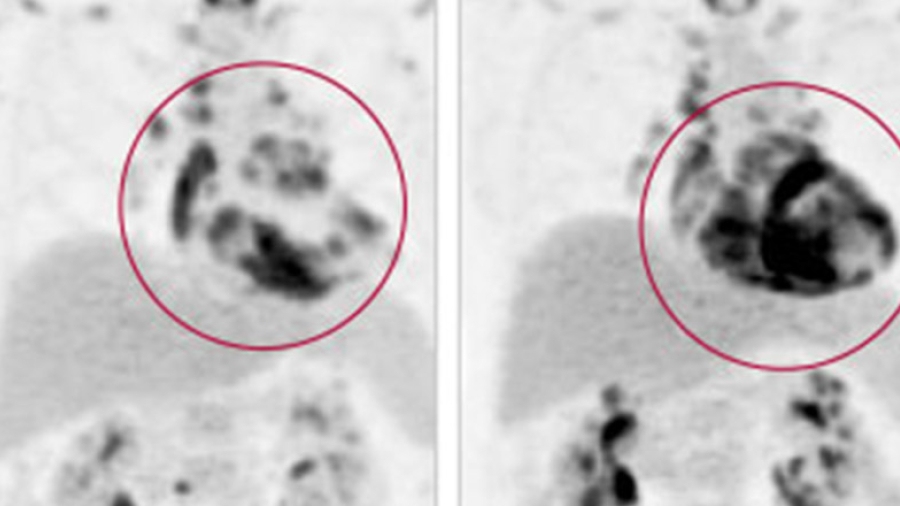

Image of cardiac sarcoidosis

November 24, 2016

Using Imaging to Diagnose and Understand Cardiac Sarcoidosis (CCC 2016)